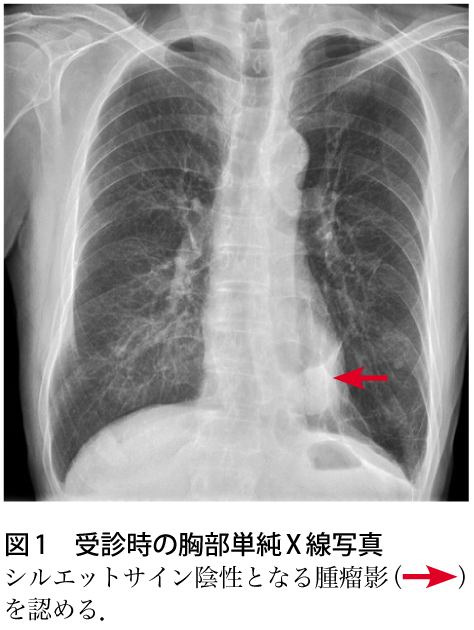

肺分画症 画像診断まとめ->画像所見 : 胸部単純 x 線写真正面像では右下肺内側が暗くなっており、右心第 2 弓の輪郭が不明瞭(シルエットアウト)。 側面像では肺門部から前肋横角に向かう紡錘形の陰影(↓)がみられる。 >診断 : 中葉無気肺 >解説 : 無気肺化した中葉は正面単純写真では右心第 2 弓を底辺と 肺分画症手術後、病理診断で肺腺がん発覚。 StageⅠB期 33歳。突然の「がんサバイバー」として病気と向き合う。 手術後の経過と備忘録。自分の気持ちを整理するためにありのままの思いをつづってみます。 日常記録も書きます。気まぐれ不定期更新です。

縦隔腫瘍、CCAM、肺分画症 著者 Author(s) 藤岡, 一路 / 芳本, 誠司 掲載誌・巻号・ページ Citation 周産期の画像診断 第二版,周産期医学 / 周産期医学編集 委員会編, Vol 43, 13 増刊号4486 刊行日 Issue date 1312 資源タイプ Resource Type Journal Article / 学術雑誌論文 版区分 Resource Version publisher 権利 Rights DOI肺分画症 硬化性血管腫 肺動静脈瘻・奇形 特発性肺線維症(ipf) 60歳過ぎた男性 60%以上 ほとんどの治療法は無効 死亡率は5年で50~70% 呼吸細気管支炎関連間質性肺疾患(rbild) 40~50歳 (やや男性に多い) 90%以上 禁煙、ステロイド 死亡はまれ 上に戻る 胸部レントゲン写真の所見別VR 画像を作成することで、さらに血管走行の詳細がはっきりする。 >診断 : 肺分画症( intralobar pulmonary sequestration ) >解説 : 分画肺は大動脈から分岐する異常動脈から血流を受け、以下の 2 型に分類される。原則として正常気管支とは交通がない。

日々の症例 143 肺分画症 Intralobar Pulmonary Sequestration

解答 解説 血痰を主訴に来院した70歳代男性 実践 画像診断q A 羊土社 レジデントノート 実践 画像診断q A 羊土社 レジデントノート 羊土社